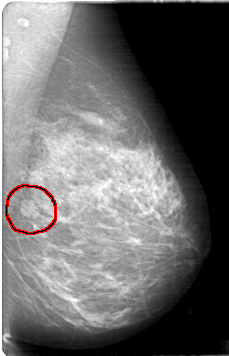

D_4082_1.LEFT_CC

FILE: D_4082_1.LEFT_CC.OVERLAY

TOTAL_ABNORMALITIES 1

ABNORMALITY 1

LESION_TYPE MASS SHAPE LOBULATED MARGINS MICROLOBULATED

ASSESSMENT 3

SUBTLETY 5

PATHOLOGY BENIGN

TOTAL_OUTLINES 1

BOUNDARY

LEFT_CC LINES 4966 PIXELS_PER_LINE 3061 BITS_PER_PIXEL 12 RESOLUTION 43.5 OVERLAY